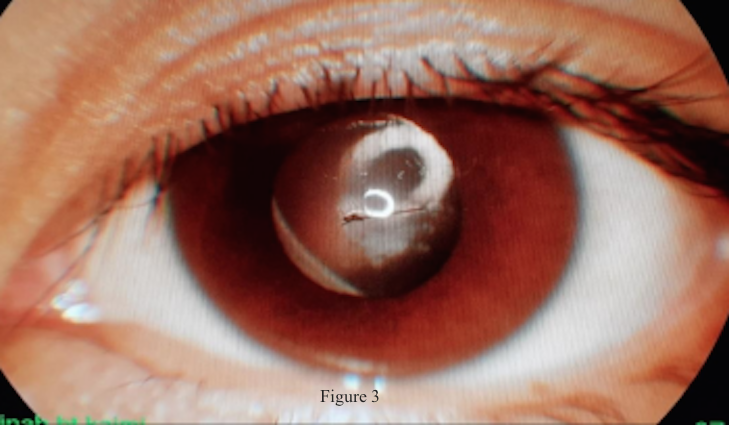

Eye injuries resulting from bird pecking are rare but may cause permanent blindness. We report a case of penetrating ocular injury following a peck by a white-breasted waterhen. A 13-year-old girl presented with painful visual loss in her left eye after being pecked by her pet bird. She sustained a central corneal laceration and traumatic cataract in her left eye. Primary closure of corneal laceration was performed without complication. Broad spectrum topical and intravenous antibiotics were administered. After two weeks, she developed a mature white cataract. Subsequently, she underwent lens aspiration with intraocular lens implantation. Her vision improved drastically from 20/2400 to 20/60. Precautions should be taken while handling birds, especially when children are handling birds, in order to prevent any ocular injury. Parents play a vital role in preventing their child from getting injured by birds.